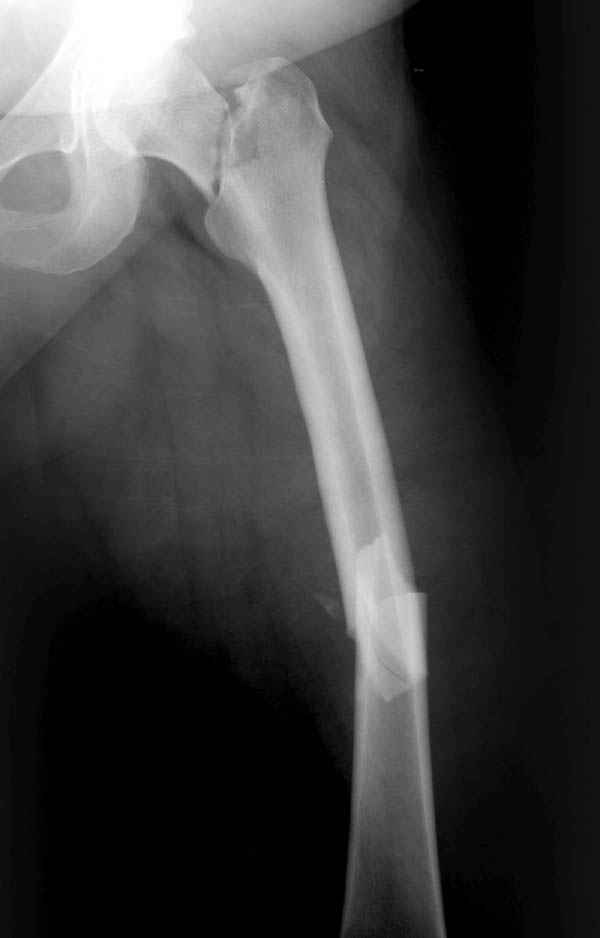

Уважаемые коллеги. Благодарим за дискуссию. Мы решили выполнить комбинированную операцию - эндопротезирование тазобедренного сустава и ретроградный интрамедуллярный остеосинтез (одномоментно)

В этом случае наилучший способ лечения - тотальное эндопротезирование тазобедренного сустава.

Наверно, вариант с вальгизирующей остеотомией с фиксацией blade plate или DHS более щадящий. А диафиз можно рефиксировать ретроградно. Или про эндопротезирование с очень длинной ножкой подумать.